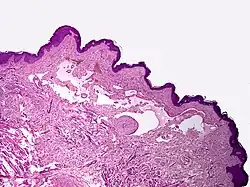

- Linfangioma cavernoso

- Lesão única na derme que pode crescer durante a infância. Geralmente na cabeça, pescoço ou extremidades. Composto por canais linfáticos dilatados, um linfangioma cavernoso tipicamente desloca tecidos e órgãos adjacentes, podendo causar disfunção.

Microscopicamente, as vesículas em um linfangioma circunscrito são canais linfáticos dilatados expandindo a derme papilar. Eles podem ser associados com acantose e hiperqueratose. Há muitos canais na derme superior, muitas vezes se estendendo para o tecido subcutâneo (a camada mais profunda da derme, contendo gordura e tecido conjuntivo). Os vasos mais profundos têm grande calibre com paredes espessas que contêm musculatura lisa. O lúmen é preenchido com fluido linfático, mas muitas vezes contém glóbulos vermelhos, linfócitos, macrófagos, e neutrófilos. Os canais são revestidos com células endoteliais planas. O interstício tem muitas células linfóides e mostra evidência de fibroplasia (a formação de tecido fibroso). Nódulos (uma pequena massa de tecido ou agregação de células) em linfangiomas cavernosos são grandes canais, irregulares, na derme reticular e tecido subcutâneo que são revestidos por uma camada única de células endoteliais e uma camada incompleta de músculo liso. O estroma é constituído por tecido conjuntivo frouxo com uma grande quantidade de células inflamatórias. Estes tumores geralmente penetram a musculatura. O higroma cístico é histologicamente indistinguível de um linfangioma cavernoso. [7]

O linfangioma cavernoso aparece pela primeira vez durante a infância, como um nódulo elástico, sem alterações da pele, na face, tronco ou extremidades. História familiar de linfangiomas anteriores é descrita.

Linfangiomas cavernosos geralmente crescem rápido, de forma semelhante aos hemangiomas.